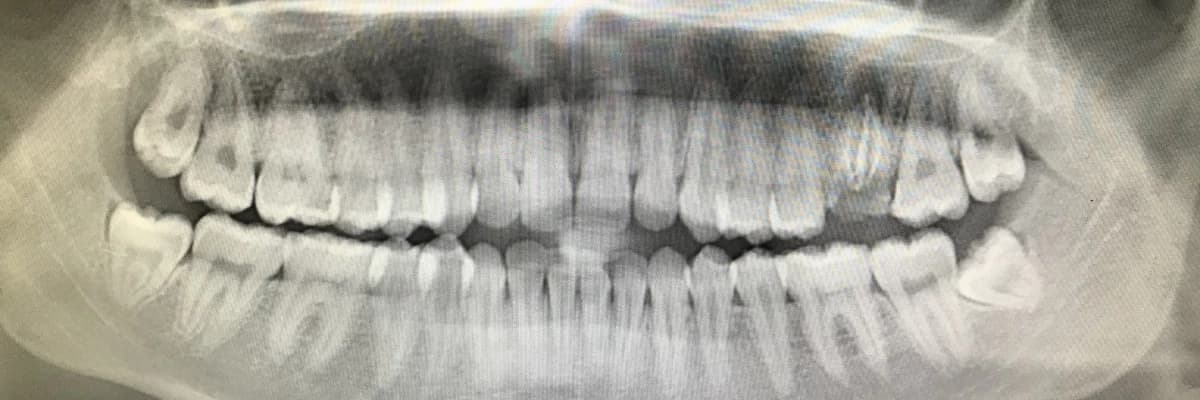

Merhaba sayın okurlarım. 10 yıllık bir hekim olarak kendi tecrübelerimden yola çıkarak konu hakkında fikrimi belirtmenin daha doğru olacağı düşüncesindeyim. Meslekte geriye dönük tedavi için bana başvuran binlerce hastada gözlemlediğim kadarıyla 20’lik dişler, diğer bir adı ile “akıl dişi “ ingilizceden gelir bu isim “Wisdom Tooth” derler, çenede oluşumu 17 yaş civarında olur ve de ağızda ort. 20’li yaşlarda görünmeye başlar. Çene içerisinde kendine yer bulamayan bu dişler genellikle gömülü olarak kalmakta ve ağrılı bir tabloyla kendini göstermektedir.

Bir uzman olarak fikrim probleme sebep vermeden gerek operasyonla gerekse ağızda düzgün konumlanamadığı durumlarda direk çekilmek suretiyle bu dişlerin çekilmelerinin daha doğru olacağı yöndedir. Toplumumuzda genellikle bir öteleme tutumu gözlemlemekteyim. Diş ağrı yaptığında ya ağrı kesici ya da antibiyotik kullanarak ağrıyı geçiştirmekte ve problem ötelenmektedir. Ancak bilinmelidir ki, mutlak suretle bu dişler bulunduğu yerlerde zararsız kalmazlar. Ya çevre yumuşak dokulara, ya komşu olduğu dişlere ya da çene eklemine zarar verirler ve hastanın problemi birden fazla olur.